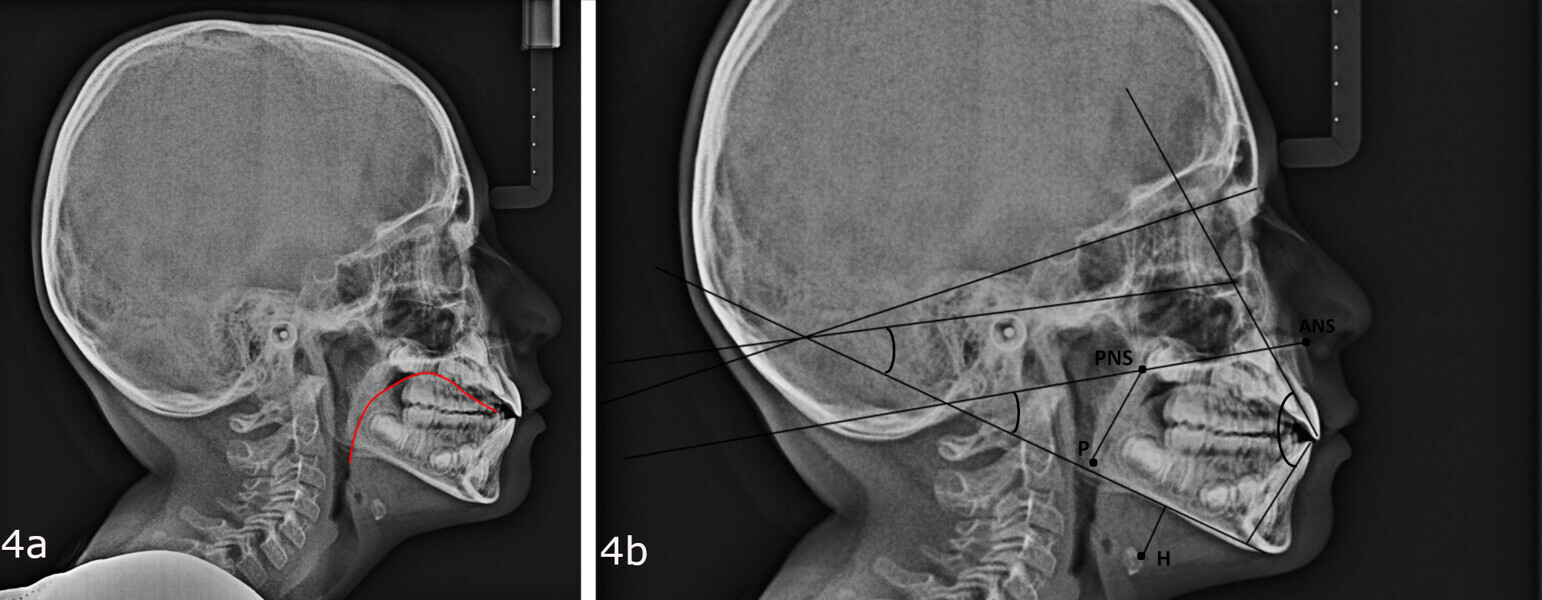

In my clinical practice, I prevent patients from rolling and rotating their heads using a cephalostat while allowing pitching: only after they have positioned themselves comfortably, do I place the post on the nasion, without exerting pressure. In this way, the patient will assume his or her habitual posture, and this too will be investigated by us. The cephalometric radiograph showed very important dysfunctional aspects (Fig. 4). Antero-rotation of the head and cervical hyper-lordosis were evident. Tracing of the tongue23 showed a very low position of the anterior part, as was found clinically. Cephalometric analysis was performed using the OrisCeph Rx1 CE program (Version 7.70; Elite Computer Italia). The patient showed a Class I skeletal pattern with antero-rotation of the maxillary plane, proclination of the mandibular incisors and increased anterior lower face height.

In the control cephalometric radiograph, the lingual position had completely regularised, the body and tip being in contact with the hard palate, creating an average overbite (Fig. 14). The cervical hyper-lordosis was moving towards correction and the skull posture was less forward.

Functional cephalometric analysis showed clear improvements too (Fig. 15; Table 1). The maxillary plane, which indicates the orientation of the maxilla, had undergone regularisation in both the angle with the skull base (SN line; going from a value of 7.7° at T0 to one of 11.2° at T1) and the angle with the Frankfort plane (going from a value of −2.9° at T0 to one of 0° at T1). The inter-incisal angle had increased, indicating an improvement in the inter-incisal ratios. The excessively divergent angle between the maxillary plane and the mandibular plane had decreased, and the facial divergence regarding both the mandibular angle and the face height index showed remarkable normalisation. Of note, was the reduction in proclination of the mandibular incisors, which went from a mandibular incisor to mandibular plane angle of 96.8° to one of 92.1°.

In agreement with Yoon et al.,4 in the radiographs at T0 and T1, we also calculated the length of the soft palate because its increase in size, as far as we know, is considered a risk factor for the development of obstructive sleep apnoea, and its reduction is part of the therapeutic goals of myofunctional therapy for the treatment of obstructive sleep apnoea.28, 29 The P–PNS value had decreased from T0 (30.0 mm) to T1 (29.4 mm). Also in agreement with Yoon et al.,4 we also calculated the length of the perpendicular from the hyoid bone to the mandibular plane. An increase indicates a low tongue posture. This line had fallen from T0 (16.3 mm) to T1 (11.9 mm), giving further confirmation of improved lingual posture.